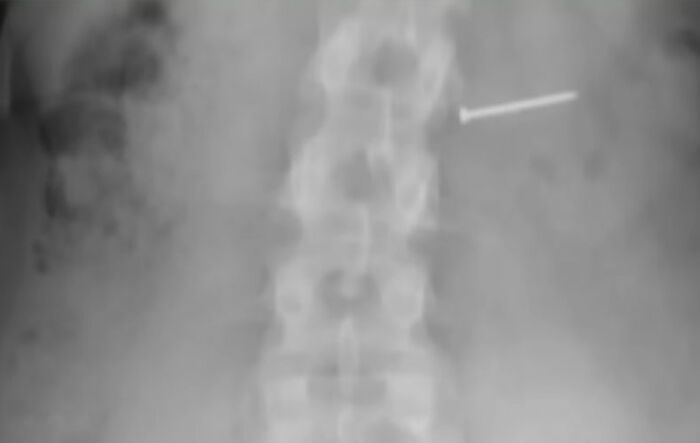

Buckley said she initially thought she had ingested pecan crumb, but went to the hospital for an X-ray just to be safe.

“It wasn’t pecan. It was a nail,” she later found out.

Image credits: Google/Marc